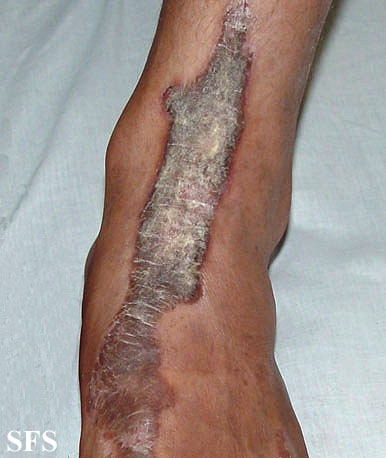

inflammatory linear verrucous epidermal naevi-bilateral